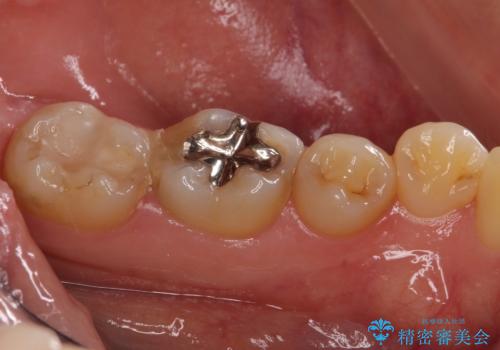

- 銀歯の周りの歯が欠けてしまい、気になるとのことで来院された患者様です。

痛みなどは特になく、診査をしたところ歯の神経に大きな問題はなかったのですが、レントゲン写真より神経に近くに迫るほど大きなむし歯があることが分かりました。

虫歯が歯髄腔(神経の部屋)に達している可能性が非常に高かったため、炎症を起こしている神経組織を部分的に切除し、歯根部分の神経組織を保存する治療法が望ましいと考えられました。

元々の銀歯も大きく装着されていたため、虫歯治療後はセラミッククラウンにて補綴することとしました。